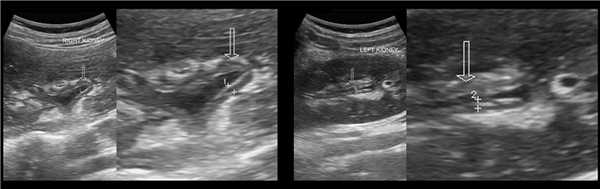

Рисунок. Пациент с острой почечной коликой. На УЗИ слева в дистальном отделе мочеточника гиперэхогенное округлое образование с акустической тенью (1), мочеточник расширен на всем протяжении (2), лоханка и большие чашечки умеренно расширены (3, 4). Заключение: Камень в дистальном отделе мочеточника. Вторичный мегоуретер и гидронефроз 2 степени.

Рисунок. На УЗИ в правой почке расширена лоханка, большие и малые чашечки, мочеточник неизменен. Левая почка и мочевой пузырь без патологических изменений. Заключение: Обструкция лоханочно-мочеточникового соединения справа. Гидронефроз справа, 3 степень.

Рисунок. Мальчик в возрасте 5-ти месяцев с инфекцией мочевыводящих путей. На УЗИ двусторонний гидронефроз 3-4 степени (1, 4), двусторонний мегауретер (2, 5). В просвете мочевого пузыря, мочеточников и ЧЛК определяется гиперэхогенная взвесь. При цистографии расширена предстательная часть мочеиспускательного канала, что указывает на клапан задней уретры. При трансперинеальном УЗИ возможно видеть задний клапан уретры. Подробнее смотри здесь.